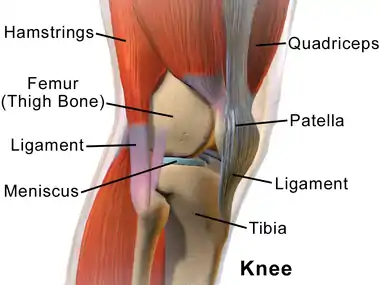

Human knees | |

Right knee seen from the right side | |

In humans and other primates, the knee joins the thigh with the leg and consists of two joints: one between the femur and tibia (tibiofemoral joint), and one between the femur and patella (patellofemoral joint).[1] It is the largest joint in the human body.[2] The knee is a modified hinge joint, which permits flexion and extension as well as slight internal and external rotation. The knee is vulnerable to injury and to the development of osteoarthritis.

The knee is a modified hinge joint, a type of synovial joint, which is composed of three functional compartments: the patellofemoral articulation, consisting of the patella, or "kneecap", and the patellar groove on the front of the femur through which it slides; and the medial and lateral tibiofemoral articulations linking the femur, or thigh bone, with the tibia, the main bone of the lower leg.[6] The joint is bathed in synovial fluid which is contained inside the synovial membrane called the joint capsule. The posterolateral corner of the knee is an area that has recently been the subject of renewed scrutiny and research.[7]